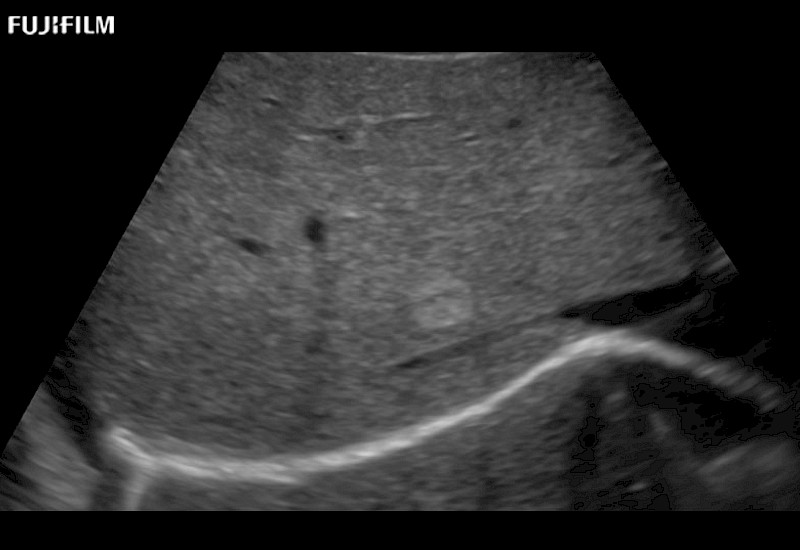

Our dedication to Laparoscopic Surgery allows us to offer superior image quality, outstanding system reliability and intuitive use of cutting edge technology.

The ARIETTA 750 incorporates all of the proven technologies and functions that medical professionals have come to expect from Fujifilm Healthcare.

ARIETTA 750 is the definitive diagnostic ultrasound solution for any clinical setting - Private Office, Imaging Center, or Hospital. The ARIETTA platform provides the ultimate in clinical performance with its state-of-the-art features and large user-friendly display.